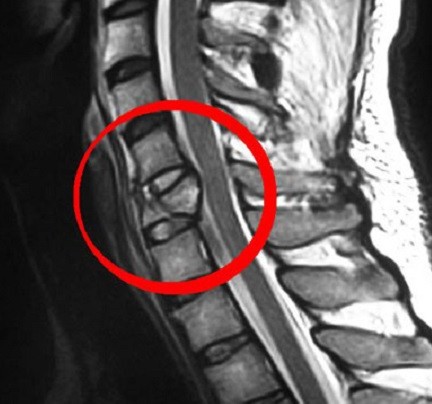

Расшифровка МРТ шейного отдела позвоночникаПосле проведения сканирования врач получает серию детальных снимков шейного отдела. Он оценивает форму и размеры позвонков, состояние позвоночного канала, высоту межпозвонковых дисков, утолщенность связок и прочее. Оценивается также структура спинного мозга, возможная деформация суставов позвоночника, наличие склеротических изменений суставных фасеток, наличие инородных тел и прочее. На основании сравнения полученных данных и физиологических норм врач делает заключение, которое не является окончательным диагнозом.